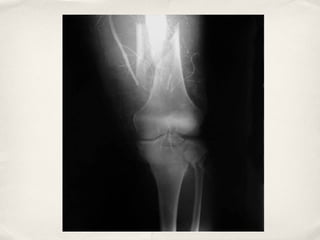

Lower Extremity